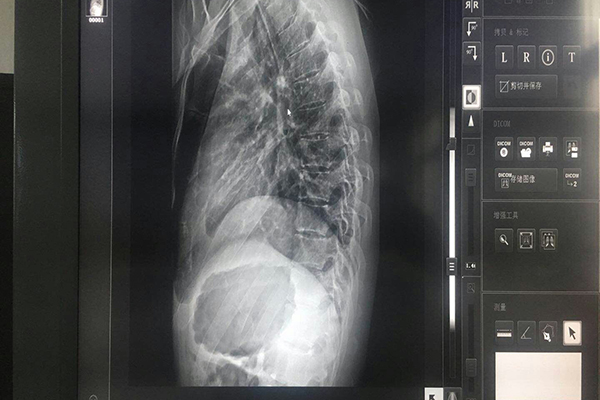

醫(yī)療灰階監(jiān)視器能夠通過專用的校正儀和校正軟件對顯示器的輸入和輸出進(jìn)行曲線校正,使之符合DICOM曲線。用顯示器有:10 bit-1024灰階,用于顯示X光灰階圖象,與診斷相關(guān),要求:10bit11bit(1024*2048灰階)。支持BBS功能(穩(wěn)定的亮度控制)。